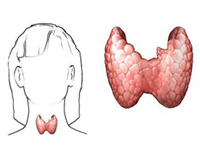

先天性甲状腺功能减低症

疾病介绍:先天性甲状腺功能减低症(简称甲低)又称克汀病或呆小病,多见于先天甲状腺缺陷,主要表现为体格和精神发育障碍,早期诊断和治疗可防止症状的发生或发展…【详细】